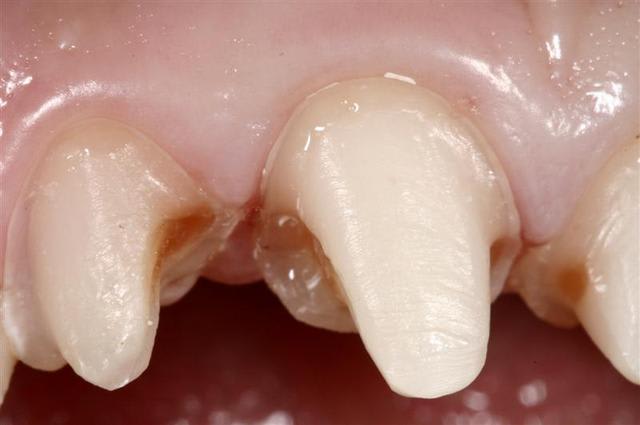

Quattres Empress 2...

et collées ...

Il y a eu blanchiment

Pour info les compo avaient des vis intra dentinaire.. Encore un qui croyait pas dans le collage..

non, en plus là j'ai fait un petit alignement des collets des centrales... donc différé de 15 jours...

La patiente n'est pas fumeuse...la gencive est parfaitement saine. L'empreinte est un jeu d'enfant.

Pour les cas esthétique comme cela il vaut mieux prendre son temps...